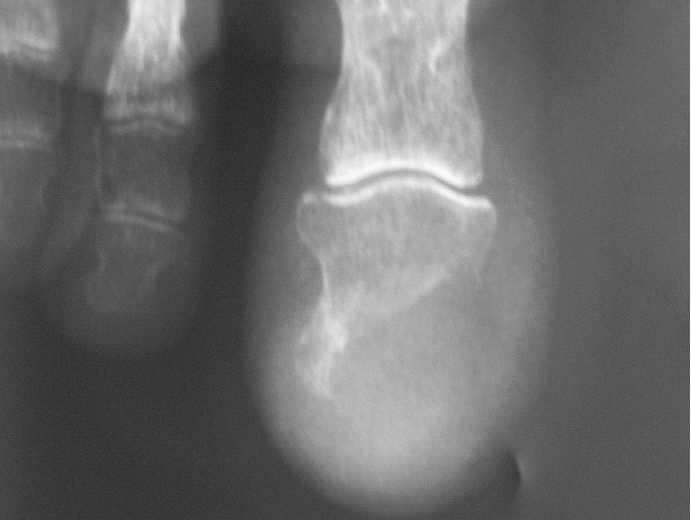

Un varón de 88 años, con antecedentes de demencia e hipertensión arterial, consultó por la aparición de una lesión muy dolorosa, de 3 meses de evolución, en el primer dedo del pie izquierdo, de rápido crecimiento. Había realizado tratamiento con antibióticos tópicos y orales sin mejorar. En la exploración se observaba una placa ulcerada, rojiza y exudativa que afectaba el extremo distal del dedo con destrucción ungueal (fig. 1). Con la sospecha de tumor maligno primario o metastásico, se realizó estudio radiológico y biopsia. En la radiografía se observaba una lesión lítica que destruía totalmente el extremo de la falange distal del primer dedo respetando la articulación interfalángica, apoyando el diagnóstico de un tumor maligno (fig. 2). En el estudio histológico, la epidermis estaba ulcerada parcialmente y a nivel de la dermis se evidenciaba una proliferación de células neoplásicas de aspecto epitelial, con abundantes mitosis y atipia nuclear (figs. 3 y 4). Algunas de estas células eran positivas con la tinción con ácido peryódico de Schiff (PAS). La tinción con citoqueratinas fue positiva. Ante la posibilidad de que se tratara de una metástasis acral, se realizó tomografía computarizada (TC) toracoabdominopélvica en la que se objetivó una gran tumoración de más de 7 cm de diámetro en el lóbulo inferior izquierdo, un nódulo de 1 cm en el lóbulo posterior derecho compatible con metástasis y adenopatías hiliares. El estudio abdominopélvico fue normal. Con estos datos se realizó el diagnóstico de carcinoma de pulmón con metástasis digital acral. Debido al intenso dolor que provocaba la metástasis se amputó el primer dedo del pie. El paciente falleció a las pocas semanas.

Fig. 2.--Radiografía del dedo afectado en la que se observa osteolisis de la falange distal sin reacción perióstica asociada.